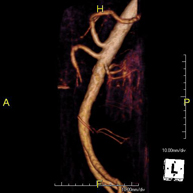

- Angio-RM Aorta abdominal

Prueba diagnóstica no invasiva que consiste en el estudio de la arteria aorta abdominal, obteniendo imágenes de alta definición anatómica mediante el empleo de un campo electromagnético y ondas de radio (con un emisor y un receptor). Es indispensable el uso de contraste paramagnético (Gadolinio). Sin embargo, no utiliza radiación ionizante. La calidad de las imágenes permite realizar reconstrucciones en 2D y 3D. Está indicado en aquellos pacientes con enfermedad vascular (aterosclerosis), estudio de aneurismas, en estudios pre-quirúrgicos de lesiones adyacentes a la aorta abdominal como "mapa" vascular, etc.

- Angio RM Aorta-ilíaca

Prueba diagnóstica no invasiva que consiste en el estudio de la arteria aorta abdominal de las arterias ilíacas, obteniendo imágenes de alta definición anatómica mediante el empleo de un campo electromagnético y ondas de radio (con un emisor y un receptor). Es indispensable el uso de contraste paramagnético (Gadolinio). Sin embargo, no utiliza radiación ionizante. La calidad de las imágenes permite realizar reconstrucciones en 2D y 3D. Esta prueba está especialmente indicada como estudio pre-quirúrgico (mapa vascular) antes de intervenciones percutáneas o quirúrgicas de aorta abdominal y arterias ilíacas, estudio complementario en pacientes con isquemia de miembros inferiores, etc.